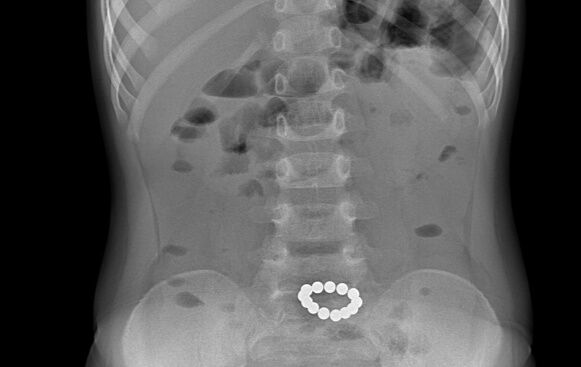

«Ребенок, играя, заглатывает шарики из конструктора порциями. В кишечнике они склеиваются, сдавливая его стенки, что приводит к некрозу тканей», — поясняет Пейливанов.

Зачастую родители не сразу замечают опасность, списывая боли в животе на погрешности в питании. Симптомы интоксикации появляются позже, и дети попадают в больницу уже с запущенной проблемой, требующей срочного оперативного вмешательства.

«В худшем случае, ребенок может нуждаться в установке стомы, а в будущем ему грозит непроходимость кишечника», — подчеркивает хирург.